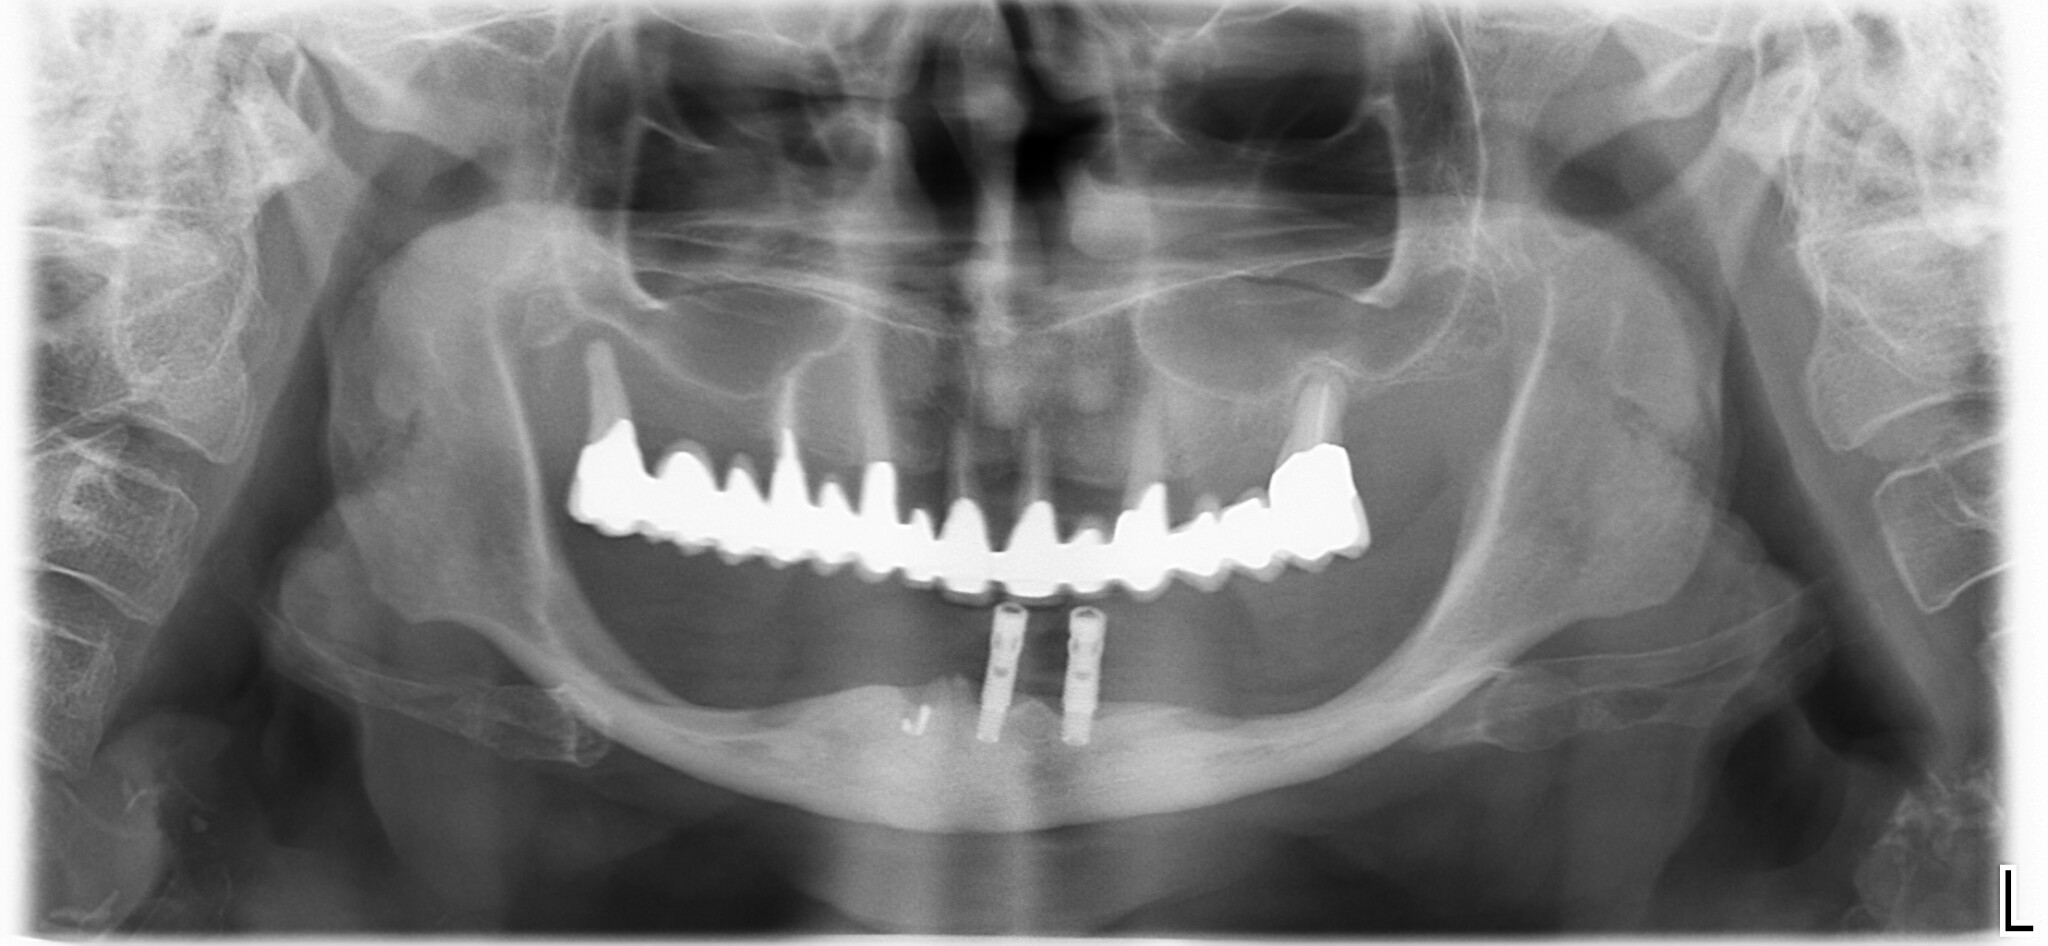

La paziente ritratta in questa panoramica arrivò da me più di tre anni fa.

lamentava il fatto che la situazione era ormai insostenibile ed era convinta di non poter mettere impianti perché la situazione della mandibola era troppo compromessa.

Chiacchierando un po’ venne fuori che non uno, ma molti colleghi avevano detto alla signora che non c’era nulla da fare.

Se fino a quel punto non era saltata fuori una soluzione significa che i colleghi che l’avevano vista in precedenza erano veramente convinti che non ci fosse nulla da fare, o forse, che il caso fosse troppo complesso e incasinato.